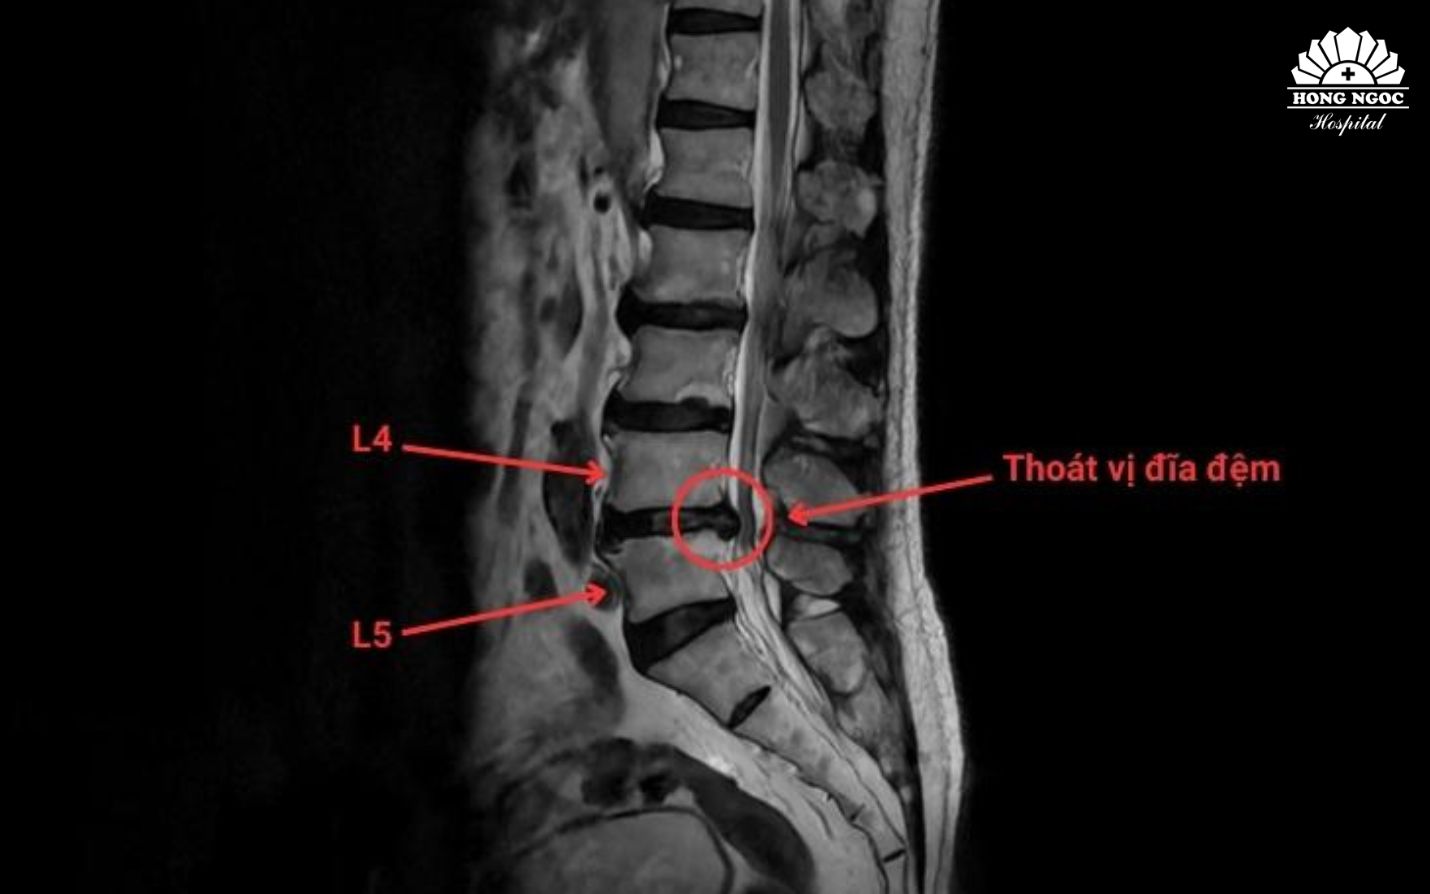

Phim chụp thoát vị đĩa đệm cột sống thắt lưng L4/L5

Thoát vị đĩa đệm là một trong những bệnh lý cột sống phổ biến, không chỉ gặp ở người cao tuổi mà đang có xu hướng trẻ hóa, ảnh hưởng đến khả năng vận động, sinh hoạt và chất lượng cuộc sống của người bệnh. Bên cạnh điều trị nội khoa và phẫu thuật, hiện nay hai phương pháp can thiệp ít xâm lấn là tiêm thẩm phân và đốt sóng cao tần (RFA) được xem là giải pháp tối ưu trong điều trị thoát vị đĩa đệm. Điểm chung của các kỹ thuật này là tác động chính xác vào vị trí gây đau dưới hướng dẫn của hệ thống chẩn đoán hình ảnh, giúp giảm đau nhanh, giảm chèn ép rễ thần kinh mà không cần phẫu thuật, đặc biệt phù hợp với người cao tuổi, có nhiều bệnh lý nền.